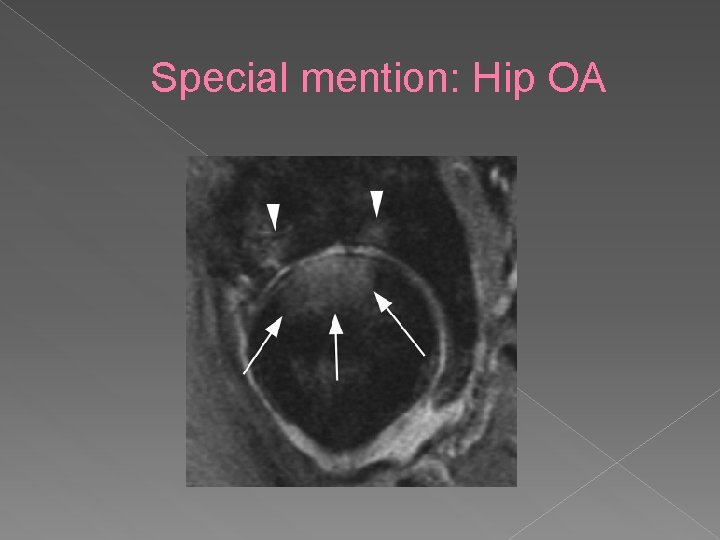

Special mention: Hip OA Hip – spherical structure • Thin covering of articular cartilage • More difficult assessment than the knee • Other features seen: • › › Labral changes/hypertrophy Paralabral cysts Loose bodies Dysplasia

Special mention: Hip OA

Special mention: Hip OA